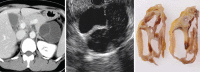

Endoscopic ultrasound (EUS) is a key modality for the evaluation of suspected pancreatic cystic neoplasms (PCNs), as the entire pancreatic gland can be demonstrated with high spatial resolution from the stomach and duodenum. Detailed information can be acquired about the internal contents of the cyst(s) [septum, capsule, mural nodules (MNs)], its relation with the main pancreatic duct (MPD), and any parenchymal changes in the underlying gland. PCNs comprise true cysts and pseudocysts. True cysts can be neoplastic or nonneoplastic. Here, we describe serous cystic neoplasm (SCN), mucinous cystic neoplasm (MCN), and intraductal papillary mucinous neoplasm (IPMN) as prototype neoplastic cysts, along with nonneoplastic lymphoepithelial cysts (LECs).